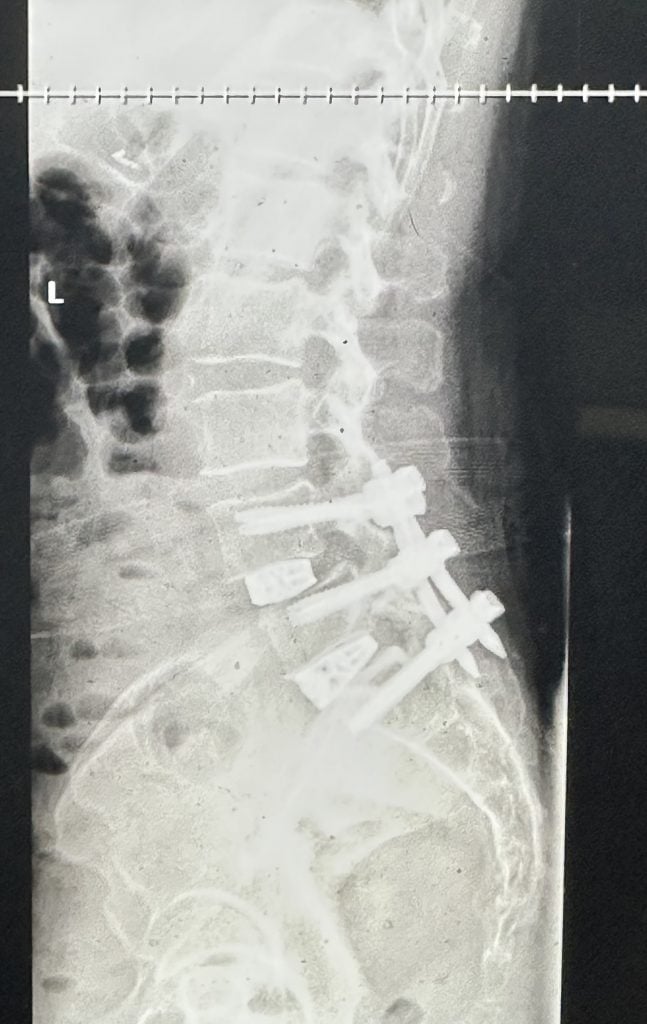

I was a very active 20 something with a fiance and a young son. Paintball, running, etc. I unfortunately had a car accident in November of 2006. My L4/L5 was herniated and prolapsed, had massive sciatic pain and lots of numbness in my legs. After trying many non surgical treatments for four years, I had a fusion completed at an area hospital in mid-2010 and revised 6 months later, only to have the fusion fail yet again. The screws had loosened and bone never grew. In 2013, my stepsister insisted I call HSS. Dr. Huang saw me and took on my case. February 2014 they completely revised my fusion with new hardware and an ALIF. Now two years later I stepped back onto the paintball field with my teammates and my now teenage son who was playing for the first time. Fully healed and feeling great, I got to share a unique sport with him and show him I am truly Back In The Game. We had so much fun together. We are also a family of five, so I can truly enjoy my wife and all three of my kids.